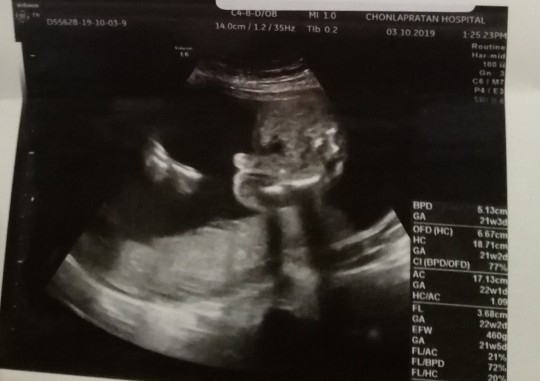

5เดือนคับผม